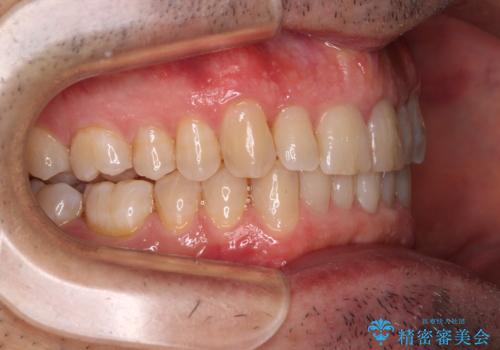

【モニター】前歯のデコボコを治したい インビザライン矯正治療

- 患者様

- 40代男性

- 矯正装置

- インビザライン

- 前歯のデコボコを気にして来院された患者様です。

インビザラインでもワイヤー装置でも対応可能でしたが、仕事の都合で来院回数を減らしたいとのことでインビザラインによる矯正治療を選択されました。

著しく咬合力が強いため、奥歯がしっかりと噛めずに治療が長引くことが懸念されました。

1セット目のインビザラインを使用した際には左右ともに大臼歯が咬み合っていなかったのですが、2セット目できっちりと仕上げることができました。